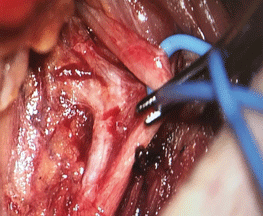

Für die atemsynchrone Hypoglossus-Stimulation müssen einzelne Äste des Nerven präpariert werden. Für die atemsynchrone Hypoglossus-Stimulation müssen einzelne Äste des Nerven präpariert werden. © Verse T, Wiest G. Hamburger Ärzteblatt 2021; 75: 12-16 © Hamburger Ärzteverlag, Hamburg